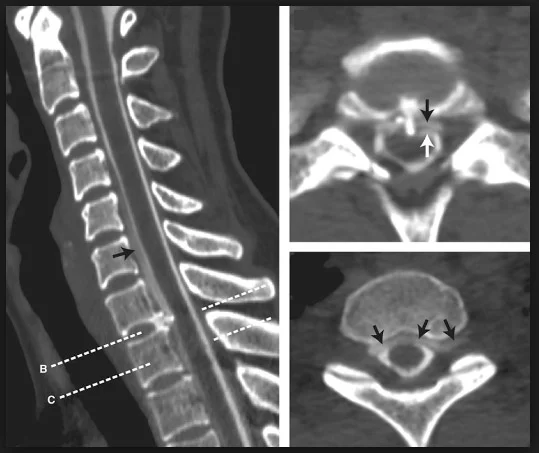

Dysphagia and Hypertrophic Spurring of the Cervical Spine | NEJM

Cervical myelopathy – MRI – Radiology at St. Vincent’s University Hospital